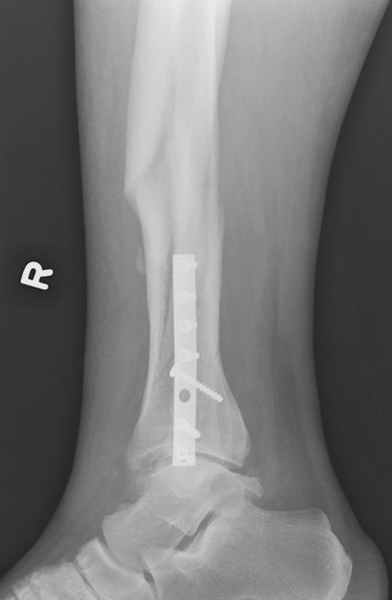

спрашивает что делать с больным который поступил недавно, фермер 55 лет падение при пьяной драке в баре, года два назад перенес операцию на лодыжке, на снимках и КТ перелом без вовлечения сустава,

Здесь мы использовали новый Synthes Nail с дополнительными дырками, в проксимальной части 4: по две косых и поперечные (один стандартный а другой динамический), в дистальной части две поперечные, прямая и косая. Вес больного более 120 кг, нагрузку начнем через месяц.

При такий спирали задний край tibia может быть сломан - нет ли этого в данном случае? На всякий случай можно было ввести 1-2 винта 4,5 мм спереди назад мимо гвоздя. Хотя самый дистальный блокирующий винт, возможно, зацепил этот отломок. А какой тут диаметр гвоздя и locking винтов?